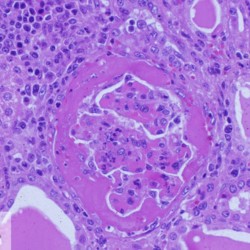

Etiquetes: B-810/96 1 total Porcine Specie: Porcine Organ: Kidney Lesion: Glomerulonephritis Lesion modifier: - Disease: Porcine dermatitis and nephropathy syndrome Files/Expedient: B-810/96 Not viewed Títol Select...Avian (Exotic) (110)Avian (Poultry) (76)Bovine (317)Canine (935)Caprine (47)Equine (257)Feline (326)Ferret (19)General (127)Marine mammal (22)Non-human primate (20)Ovine (328)Porcine (379)Rabbit (61)Reptile (38)Rodent (28)Wildlife (91) Format Select...- (60)Abomasum (37)Adrenal gland (10)Blood (7)Blood vessel (50)Body as a whole (19)Bone (57)Bone marrow (21)Brain (93)Cloaca (1)Diaphragm (2)Ear (5)Esophagus (39)Eye (16)Fetus (12)Gallbladder (23)Gizzard (2)Heart (265)Intestine (356)Joint (32)Kidney (443)Larynx (5)Liver (326)Lung (264)Lymph node (91)Mammary gland (10)Mediastinum (1)Muscle (22)Nasal cavity (22)Nerve (7)Omasum (5)Oral cavity (63)Ovary (14)Oviduct (8)Pancreas (7)Parathyroid (5)Penis (10)Peritoneum (65)Pharynx (9)Pituitary gland (6)Placenta (7)Prostate (8)Proventriculus (3)Reticulum (1)Rumen (28)Sinus (7)Skin (181)Spinal cord (15)Spleen (105)Stomach (125)Teeth (1)Testicle (11)Thoracic cavity (31)Thymus (13)Thyroid gland (5)Tongue (32)Tonsils (11)Trachea (11)Urethra (5)Urinay bladder (61)Uterus (27)Vagina (1)Vulva (1)Yolk sac (1) Cobertura Select...- (152)Abomasitis (26)Abscess (27)Acidosis (1)Adenocarcinoma (20)Adenoma (9)Aerosacculitis (6)Agenesis (1)Agnathia (1)Alopecia (7)Amyloidosis (12)Aneurysm (6)Angiectasis (1)Anthracosis (1)Arteritis (11)Arthritis (15)Arthrogryposis (6)Artifact (4)Ascites (13)Atelectasis (8)Atherosclerosis (5)Atresia (1)Atrial septal defect (2)Atrophy (10)Autolysis (7)Bronchitis (6)Bronchopneumonia (26)Cachexia (2)Carcinoma (103)Cardiomyopathy (19)Cellulitis (2)Chemodectoma (4)Cholangiohepatitis (4)Cholangitis (19)Cholecystitis (4)Cholestasis (5)Chondrodysplasia (2)Chondrosarcoma (2)Chronic passive congestion (13)Chylothorax (2)Cirrhosis (6)Coelomitis (3)Coenurus cerebralis (4)Colitis (40)Congestion (17)Conjunctivitis (5)Coronitis (3)Cryptorchidism (3)Cyst (25)Cystitis (24)Dermatitis (69)Diaphragmatic hernia (4)Dilation (28)Discospondylitis (1)Disseminated intravascular coagulation (7)Dyschondroplasia (1)Dysplasia (29)Ectopia cordis (1)Ectopic ureter (1)Edema (55)Emphysema (5)Encephalitis (5)Endocardiosis (14)Endocarditis (26)Endometritis (5)Enteritis (118)Enterolith (6)Epulis (3)Esophagitis (14)Fasciitis (1)Fibrosis (7)Fibrous osteodystrophy (8)Fistula (1)Folliculitis (3)Fracture (2)Gastritis (34)Gingivitis (5)Glioma (8)Glomerulonephritis (21)Glossitis (25)Glycogenosis (1)Gout (8)Granuloma (2)Granulosa cell tumor (4)Hemangioma (9)Hemangiosarcoma (46)Hematoma (8)Hemoglobinuria (2)Hemopericardium (12)Hemoperitoneum (2)Hemorrhage (100)Hemosiderosis (7)Hemothorax (2)Hepatitis (78)Hernia (11)Histiocytosis (3)Hydatid cyst (11)Hydrocephalus (9)Hydrometra (1)Hydronephrosis (22)Hydropericardium (6)Hydrothorax (3)Hydroureter (5)Hyperkeratosis (8)Hyperostosis (4)Hyperplasia (37)Hypertrophy (9)Hypopigmentation (1)Hypoplasia (7)Hypopyon (1)Impaction (6)Infarction (63)Insulinoma (6)Intussusception (5)Jaundice (17)Laminitis (2)Laryngitis (2)Leiomyoma (5)Leukemia (13)Lipidosis (36)Lipoma (7)Lymphadenitis (45)Lymphadenopathy (7)Lymphangiectasia (6)Lymphangitis (5)Lymphoma (221)Malacia (11)Malignant melanoma (15)Mast cell tumor (11)Mastitis (8)Megaesophagus (2)Melanosis (3)Melena (4)Meningioma (6)Meningitis (6)Meningocele (2)Meningoencephalitis (5)Mesothelioma (5)Methemoglobinemia (2)Mineralization (10)Mucocele (5)Mucometra (1)Multilobular bone tumor (1)Mummification (3)Myelofibrosis (1)Myocarditis (4)Myositis (5)Necrosis (81)Nephritis (113)Nephroblastoma (6)Nephrosclerosis (1)Nephrosis (14)Neuritis (1)Obstruction (13)Omasitis (4)Omphalitis (1)Omphalophlebitis (7)Orchitis (4)Osteoarthrosis (5)Osteomyelitis (9)Otitis (2)Palatoschisis (3)Pancreatitis (3)Panniculitis (3)Papilloma (7)Parakeratosis (14)Patent ductus arteriosus (6)Peliosis hepatis (1)Perforation (17)Pericarditis (35)Peritonitis (39)Persistent right aortic arch (1)Pharyngitis (2)Pheochromocytoma (2)Phlebitis (2)Placentitis (6)Pleuritis (21)Pleuropneumonia (24)Pneumonia (109)Pneumothorax (3)Polycystosis (14)Polyp (5)Polyserositis (6)Posthitis (1)Proctitis (4)Prolapse (3)Prostatitis (3)Proventriculitis (1)Pyelonephritis (24)Pyometra (6)Pyothorax (4)Rhinitis (11)Rumenitis (6)Rupture (24)Salpingitis (3)Sarcoma (57)Sclerosis (1)Scoliosis (2)Seminoma (2)Sequestrum (2)Serous atrophy (14)Sinusitis (7)Splenitis (14)Splenomegaly (9)Spondylitis (6)Spondylosis (1)Stenosis (9)Stomatitis (32)Tenosynovitis (2)Teratoma (3)Thricobezoar (2)Thrombosis (16)Tonsilitis (4)Torsion (13)Tracheitis (4)Tympany (7)Typhlitis (8)Typhlocolitis (4)Ulcer (43)Urethritis (1)Urolithiasis (36)Uroperitoneum (1)Uveitis (1)Vasculitis (15)Ventricular septal defect (3)Volvulus (11) Matèria Select... - (14)- (1653)- (152)Abomasitis - Catarrhal (2)Abomasitis - Catarrhal-hemorrhagic (1)Abomasitis - Chronic (1)Abomasitis - Fibrinous-necrotizing (2)Abomasitis - Hyperplasic (5)Abomasitis - Hyperplasic - Chronic (1)Abomasitis - Necrotic (1)Abomasitis - Necrotizing (2)Abomasitis - Ulcerative (5)Adenocarcinoma (9)Aerosacculitis - Granulomatous (1)Amyloidosis - Chronic (1)Arteritis - Necrotic (2)Arteritis - Necrotizing (1)Arthritis - Chronic (4)Arthritis - Fibrinous-purulent (3)Arthritis - Serous (4)Arthritis - Subacute (1)Ascites - Serous (1)Atrophy - Serous (1)Bronchitis - Catarrhal (3)Bronchitis - Suppurative (1)Bronchopneumonia - Catarrhal-purulent (17)Bronchopneumonia - Fibrinous (1)Bronchopneumonia - Granulomatous (1)Bronchopneumonia - Purulent (1)Bronchopneumonia - Suppurative (5)Carcinoma - Adenocarcinoma (33)Carcinoma - Adenocarcinoma - Hepatocellular (2)Carcinoma - Adenocarcinoma - Mucinous (1)Carcinoma - Basosquamous (1)Carcinoma - Cholangiocellular (3)Carcinoma - Hepatocellular (4)Carcinoma - Metastatic (3)Carcinoma - Squamous cell carcinoma (13)Carcinoma - Transitional cell (2)Cardiomyopathy - Dilated (13)Cardiomyopathy - Hypertrophic (6)Cellulitis - Necrotizing (1)Cholangitis - Chronic (8)Cholangitis - Hyperplasic (3)Cholecystitis - Fibrinous-necrotizing (1)Coelomitis - Fibrinous (1)Coelomitis - Granulomatous (1)Colitis - Catarrhal (3)Colitis - Catarrhal-hemorrhagic (1)Colitis - Fibrinous (1)Colitis - Fibrinous-necrotizing (1)Colitis - Fibrinous-necrotizing (Diphtheritic) (6)Colitis - Granulomatous (2)Colitis - Hemorrhagic (4)Colitis - Hemorrhagic-necrotizing (3)Colitis - Necrotizing (2)Colitis - Ulcerative (6)Congestion - Chronic (2)Conjunctivitis - Hyperplasic (1)Conjunctivitis - Purulent (3)Coronitis - Ulcerative (1)Cystitis - Chronic (3)Cystitis - Fibrinous (1)Cystitis - Fibrinous-necrotizing (1)Cystitis - Follicular (1)Cystitis - Hemorrhagic (6)Cystitis - Hemorrhagic-ulcerative (1)Cystitis - Necrotizing (9)Cystitis - Perforated (1)Dermatitis - Granulomatous (14)Dermatitis - Hyperkeratotic (10)Dermatitis - Hyperplasic (proliferative) (1)Dermatitis - Hyperplastic (10)Dermatitis - Necrotizing (4)Dermatitis - Pustular (4)Dermatitis - Ulcerative (2)Dilation - Chronic (1)Discospondylitis - Necrotizing (1)Dysplasia - Follicular (5)Edema - Interstitial (6)Emphysema - Interstitial (1)Encephalitis - Granulomatous (1)Encephalitis - Nonsuppurative (1)Endocardiosis - Mitral (7)Endocardiosis - Mitral - Chronic (5)Endocarditis - Valvular (6)Endocarditis - Valvular - Mitral (7)Endocarditis - Valvular - Pulmonic (1)Endocarditis - Valvular - Subacute (1)Endocarditis - Valvular - Subaortic (5)Endocarditis - Valvular - Tricuspid (4)Endometritis - Purulent (3)Endometritis - Purulent-hemorrhagic (2)Enteritis - Catarrhal (23)Enteritis - Catarrhal - Acute (1)Enteritis - Catarrhal-hemorrhagic (5)Enteritis - Catarrhal-hemorrhagic - Acute (2)Enteritis - Fibrinous (16)Enteritis - Fibrinous - Acute (3)Enteritis - Fibrinous-necrotizing (7)Enteritis - Granulomatous (14)Enteritis - Granulomatous - Chronic (1)Enteritis - Granulomatous - Multifocal (1)Enteritis - Hemorrhagic (17)Enteritis - Hemorrhagic - Acute (1)Enteritis - Hemorrhagic-necrotizing (1)Enteritis - Hyperplasic (proliferative) (4)Enteritis - Necrotizing (4)Enteritis - Necrotizing - Acute (1)Enteritis - Necrotizing - Hemorrhagic (1)Enteritis - Necrotizing-ulcerative (2)Enteritis - Ulcerative (1)Enteritis - Ulcerative-hemorrhagic (1)Esophagitis - Erosive-ulcerative (6)Esophagitis - Necrotizing (4)Esophagitis - Ulcerative (1)Esophagitis - Ulcerative-necrotizing (1)Fasciitis - Fibrinous-purulent (1)Folliculitis - Purulent (2)Gastritis - Catarrhal (2)Gastritis - Chronic (1)Gastritis - Follicular (1)Gastritis - Hemorrhagic (2)Gastritis - Hemorrhagic-necrotizing (1)Gastritis - Hypertrophic (2)Gastritis - Inclusion bodies (1)Gastritis - Mineralization (1)Gastritis - Mycotic (1)Gastritis - Necrotizing (2)Gastritis - Ulcerative (6)Gastritis - Uremic (3)Gingivitis - Erosive (2)Gingivitis - Hyperplasic (proliferative) (1)Gingivitis - Necrotizing (1)Glomerulonephritis - Chronic (7)Glomerulonephritis - Membranoproliferative (3)Glomerulonephritis - Membranoproliferative - Chronic (1)Glomerulonephritis - Membranous (3)Glomerulonephritis - Membranous - Chronic (1)Glomerulonephritis - Proliferative (2)Glomerulonephritis - Subacute (1)Glossitis - Erosive (2)Glossitis - Granulomatous (6)Glossitis - Hyperplasic (1)Glossitis - Hyperplasic (proliferative) (2)Glossitis - Hyperplastic (1)Glossitis - Necrotizing (2)Glossitis - Necrotizing - Focal (1)Glossitis - Ulcerative (6)Glossitis - Ulcerative - Multifocal (1)Glossitis - Ulcerative - Subacute (1)Glycogenosis (1)Granuloma - Eosinophilic (1)Hemangiosarcoma - Metastatic (2)Hemorrhage - Acute (1)Hemorrhage - Subcapsular (3)Hepatitis - Abscess (9)Hepatitis - Acute (3)Hepatitis - Chronic (4)Hepatitis - Chronic interstitial (6)Hepatitis - Granulomatous (7)Hepatitis - Interstitial - Multifocal (1)Hepatitis - Interstitial - Subacute (1)Hepatitis - Necrotizing (17)Hepatitis - Necrotizing - Acute (2)Hepatitis - Necrotizing - Hemorrhagic (1)Hepatitis - Necrotizing - Subacute (1)Hepatitis - Pyogranulomatous (7)Hepatitis - Subacute (4)Hydronephrosis - Chronic (1)Hydropericardium - Chronic (1)Hyperplasia - Erythroid (1)Hyperplasia - Lymphoid (3)Hyperplasia - Myeloid (1)Hyperplasia - Nodular (8)Hypertrophy - Concentric (2)Hypertrophy - Eccentric (3)Infarction - Acute (17)Infarction - Acute - Multifocal (2)Infarction - Chronic (5)Infarction - Chronic - Multifocal (1)Infarction - Subacute (18)Infarction - Subacute - Focal (2)Laminitis - Chronic (2)Laryngitis - Necrotic (1)Laryngitis - Necrotizing (1)Leukemia - Lymphoid leukemia (2)Leukemia - Non-lymphoid leukemia (6)Lipidosis - Multifocal (1)Lipidosis - Panlobular (1)Lipidosis - Panlobular - Generalized (2)Lymphadenitis - Granulomatous (24)Lymphadenitis - Granulomatous - Chronic (3)Lymphadenitis - Hemorrhagic (1)Lymphadenitis - Necrotizing (5)Lymphadenitis - Necrotizing (caseous) (11)Lymphangitis - Granulomatous (1)Lymphangitis - Purulent (1)Lymphangitis - Ulcerative (1)Lymphoma - Alimentary lymphoma (7)Lymphoma - Cutaneous lymphoma (6)Lymphoma - Lymphosarcoma (2)Lymphoma - Mediastinal lymphoma (1)Lymphoma - Multicentric lymphoma (29)Malignant melanoma - Malignant (1)Malignant melanoma - Metastatic (1)Mast cell tumor - Metastatic (1)Mastitis - Fibrinous-purulent (2)Mastitis - Necrotic (1)Mastitis - Purulent (3)Mastitis - Suppurative (1)Meningitis - Fibrinous-purulent (2)Meningitis - Purulent (4)Meningoencephalitis - Necrotizing (3)Meningoencephalitis - Nonsuppurative (2)Mineralization - Metastatic (4)Myocarditis - Fibrous - Chronic (1)Myocarditis - Granulomatous (1)Myositis - Purulent (2)Necrosis - Acute (1)Necrosis - Cortical (5)Necrosis - Follicular (1)Necrosis - Papillary (8)Necrosis - Papillary - Acute (3)Necrosis - Subacute (3)Necrosis - Tubular (6)Nephritis - Embolic (2)Nephritis - Embolic suppurative (7)Nephritis - Granulomatous (27)Nephritis - Granulomatous - Chronic (1)Nephritis - Granulomatous - Multifocal (1)Nephritis - Interstitial (6)Nephritis - Interstitial - Acute (4)Nephritis - Interstitial - Chronic (41)Nephritis - Interstitial - Subacute (12)Nephritis - Purulent (7)Nephritis - Purulent - Acute (2)Nephritis - Purulent - Multifocal (3)Nephrosis - Cholemic (3)Nephrosis - Hemoglobinuric (10)Omasitis - Fibrinous-necrotizing (1)Omasitis - Hyperkeratotic (1)Omasitis - Necrotizing (2)Omphalophlebitis - Fibrinous-purulent (2)Omphalophlebitis - Purulent (3)Orchitis - Necrotizing (1)Osteomyelitis - Necrotizing (7)Osteomyelitis - Purulent (2)Otitis - Necrotizing (1)Otitis - Proliferative (1)Pancreatitis - Acute (1)Pancreatitis - Chronic (1)Pancreatitis - Granulomatous (1)Panniculitis - Fibrinous-purulent (1)Panniculitis - Necrotic (1)Panniculitis - Parasitic (1)Perforation - Acute (2)Pericarditis - Fibrinous (19)Pericarditis - Fibrinous - Subacute (1)Pericarditis - Fibrinous-necrotizing (1)Pericarditis - Fibrinous-purulent (3)Pericarditis - Fibrous (1)Pericarditis - Fibrous - Chronic (1)Pericarditis - Gangrenous (6)Pericarditis - Granulomatous (1)Pericarditis - Granulomatous - Chronic (2)Peritonitis - Acute (1)Peritonitis - Fibrinous (11)Peritonitis - Fibrinous - Subacute (1)Peritonitis - Fibrinous-purulent (5)Peritonitis - Fibrous (3)Peritonitis - Granulomatous (6)Peritonitis - Purulent (1)Peritonitis - Purulent-hemorrhagic (1)Peritonitis - Pyogranulomatous (3)Pharyngitis - Fibrinous-necrotizing (1)Pharyngitis - Ulcerative (1)Pheochromocytoma - Metastatic (1)Phlebitis - Purulent (1)Placentitis - Fibrinous-necrotizing (1)Placentitis - Necrotic (1)Placentitis - Necrotizing (1)Pleuritis - Chronic (1)Pleuritis - Fibrinous (3)Pleuritis - Fibrinous-purulent (2)Pleuritis - Fibrous (2)Pleuritis - Granulomatous (3)Pleuritis - Hyperplastic (2)Pleuritis - Purulent (2)Pleuritis - Pyogranulomatous (1)Pleuropneumonia - Fibrinous (13)Pleuropneumonia - Fibrinous-necrotizing (5)Pleuropneumonia - Granulomatous (2)Pleuropneumonia - Hemorrhagic-necrotizing (4)Pneumonia - Aspiration (11)Pneumonia - Bronchointerstitial (4)Pneumonia - Bronchointerstitial - Subacute (1)Pneumonia - Embolic (5)Pneumonia - Granulomatous (37)Pneumonia - Granulomatous - Multifocal (4)Pneumonia - Hemorrhagic-necrotizing (2)Pneumonia - Interstitial (7)Pneumonia - Interstitial - Acute (8)Pneumonia - Interstitial - Chronic (6)Pneumonia - Interstitial - Subacute (15)Pneumonia - Necrotizing (2)Pneumonia - Pyogranulomatous (2)Pneumonia - Verminous (5)Polyserositis - Fibrinous (6)Polyserositis - Fibrous (1)Proctitis - Fibrinous-necrotizing (1)Proctitis - Parasitic (2)Prostatitis - Purulent (1)Pyelonephritis - Acute (2)Pyelonephritis - Chronic (3)Rhinitis - Catarrhal (2)Rhinitis - Fibrinous (1)Rhinitis - Granulomatous (4)Rhinitis - Purulent (3)Rumenitis - Acute (1)Rumenitis - Erosive (1)Rumenitis - Necrotizing (1)Rupture - Acute (3)Sarcoma - Fibrosarcoma (12)Sarcoma - Hemangiosarcoma (11)Sarcoma - Histiocytic (7)Sarcoma - Metastatic (1)Sarcoma - Multilobular tumor of bone (1)Sequestrum - Chronic (2)Sinusitis - Suppurative (1)Splenitis - Granulomatous (8)Splenitis - Granulomatous - Chronic (1)Splenitis - Necrotizing (3)Splenitis - Necrotizing (caseous) (2)Spondylitis - Necrotizing (2)Stenosis - Intestinal (1)Stenosis - Valvular - Subaortic (4)Stomatitis - Erosive (12)Stomatitis - Erosive-ulcerative (3)Stomatitis - Fibrinous-necrotizing (1)Stomatitis - Fibrinous-necrotizing (Diphtheritic) (1)Stomatitis - Granulomatous (1)Stomatitis - Hyperplasic (1)Stomatitis - Hyperplasic (proliferative) (1)Stomatitis - Necrotizing (2)Stomatitis - Ulcerative (5)Stomatitis - Ulcerative - Multifocal (1)Stomatitis - Ulcerative-necrotizing (1)Tonsilitis - Necrotizing (4)Torsion - Acute passive hyperemia (5)Tracheitis - Catarrhal (3)Tracheitis - Fibrinous (1)Tracheitis - Granulomatous (1)Typhlitis - Catarrhal (1)Typhlitis - Fibrinous-necrotizing (2)Typhlitis - Hemorrhagic (2)Typhlitis - Ulcerative-hemorrhagic (1)Typhlocolitis - Fibrinous-necrotizing (2)Typhlocolitis - Proliferative (1)Ulcer - Chronic (6)Ulcer - Multifocal (2)Ulcer - Mycotic (1)Ulcer - Perforated (6)Urethritis - Hemorrhagic (1)Urolithiasis - Chronic (2)Uveitis - Granulomatous (1)Vasculitis - Granulomatous (1)Vasculitis - Necrotizing (1) Editor Select...- (1970)Acidosis (2)Actinobacillosis (Pleuropneumonia) (11)Aelurostrongylosis (2)African horse sickness (13)African swine fever (14)Alopecia X (1)Anaplasmosis (4)Anthrax (2)Aortic thromboembolism (feline) (7)Ascariasis (15)Aspergillosis (18)Atopic dermatitis (1)Atrophic rhinitis (3)Babesiosis (6)Blackhead (1)Bluetongue (11)Border disease (2)Bovine viral diarrhea (21)Brucellosis (2)Candidiasis (5)Canine distemper (14)Caprine arthritis-encephalitis (2)Capture myopathy (1)Cardiac insufficiency (17)Caseous lymphadenitis (7)Chlamydiosis (2)Classical swine fever (19)Clostridiosis (19)Coccidiosis (9)Coenurosis (4)Colibacillosis (21)Contagious ecthyma (7)Copper toxicosis (11)Cowdriosis (Heartwater) (3)Cryptococcosis (3)Cryptosporidiosis (2)Cysticercosis (23)Demodicosis (1)Diabetes (1)Dicrocoeliosis (5)Dictyocaulosis (4)Dirofilariasis (7)Discoid lupus erythematosus (3)Echinococcosis (17)Edema disease (7)Egg drop syndrome (1)Encephalitozoonosis (5)Enterotoxemia (1)Enzootic bovine leukosis (46)Epitheliogenesis imperfecta (3)Equine rhinopneumonitis (2)Equine verminous arteritis (strongylosis) (7)Erysipelas (5)Exudative epidermitis (7)Fasciolasis (11)Feline eosinophilic dermatoses (1)Feline hepatic lipidosis (8)Feline histiocytosis (4)Feline infectious peritonitis (38)Feline leukemia (4)Feline lower urinary tract disease (3)Feline panleukopenia (16)Feline viral rhinotracheitis (1)Flea allergy dermatitis (1)Foot and mouth disease (2)Gasterophilosis (4)Glasser's disease (15)Gousiekte (4)Gout (6)Haemonchosis (9)Hemolytic anemia (4)Hemorrhagic diathesis (1)Hepatic insufficiency (11)Hepatosis dietetica (7)Herpesvirosis (6)Hyperadrenocorticism (7)Hyperparathyroidism (10)Hypertrophic osteopathy (6)Hypervitaminosis D (1)Hypodermosis (1)Inclusion body hepatitis (4)Infectious bovine rhinotracheitis (5)Infectious bronchitis (5)Infectious canine hepatitis (13)Influenza (4)Juvenile nephropathy (8)Lamb dysentery (4)Leishmaniasis (28)Leptospirosis (1)Leukosis (5)Listeriosis (4)Lumpy skin disease (3)Maedi-visna (4)Malignant catarrhal fever (12)Mange (6)Mannheimiosis (5)Marek's disease (7)Metabolic bone disease (2)Mucoid enteropathy (5)Mulberry heart disease (5)Myasis (1)Mycobacteriosis (22)Mycosis fungoides (6)Myxomatosis (3)Necrobacillosis (5)Neonatal isoerythrolysis (6)Nocardiosis (4)Oestrosis (2)Onchocerciasis (1)Osteochondrosis (1)Ostertagiosis (6)Ovine pulmonary adenocarcinoma (5)Oxyuriasis (1)Pacheco's disease (4)Papillomatosis (6)Paratuberculosis (18)Parvovirosis (17)Pasteurellosis (11)Pemphigus foliaceus (1)Periodontal disease (1)Polioencephalomalacia of ruminants (4)Polyarteritis nodosa (3)Polycystic kidney disease (13)Porcine circovirosis (11)Porcine dermatitis and nephropathy syndrome (9)Porcine proliferative enteropathy (4)Porcine reproductive and respiratory syndrome (6)Porcine stress syndrome (1)Pox (13)Pregnancy toxemia (3)Proventricular dilatation disease (2)Pseudotuberculosis (yersiniosis) (2)Psittacine beak and feather disease (PBFD) (5)Pyoderma (4)Q fever (4)Rabbit hemorrhagic disease (2)Renal insufficiency (12)Reticuloendotheliosis (2)Rhodococcosis (1)Rickets (1)Rinderpest (2)Salmonellosis (34)Sarcosporidiosis (2)Schmallenberg (7)Septicemia (23)Spirocercosis (11)Streptococcosis (5)Strongylosis (1)Swine dysentery (5)Systemic coronavirosis (5)Tetralogy of Fallot (5)Theileriosis (13)Thromboembolism (5)Toxoplasmosis (11)Transmissible viral proventriculitis (1)Traumatic reticuloperitonitis (3)Traumatism (16)Tuberculosis (58)Ulcerative lymphangitis (1)Uremic syndrome (20)Viral arthritis (6)White muscle disease (9)Wobbler syndrome (2)Xanthomatosis (1)Zygomycosis (4) Idioma Select...- (1180)Bacterial (501)Degeneration (106)Fungal (46)Hemodynamic (112)Idiopathic (22)Inflammation (58)Malformation (88)Neoplasia (343)Nutritional (41)Parasitic (243)Physical/Chemical (93)Toxic (44)Viral (304) Ítem destacat Bovine Anaplasma marginale (extravascular haemolytic anemia). Blood smear abtained postmortem from cut ear capillaries.University of Pretoria, South Africa